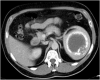

Isolated splenic cystic echinococcosis is a rare condition. In Greece the number of cases has declined substantially in the last 20 years. The spleen is the second most common extrahepatic site of cystic echinococcosis. Albendazole is safe, but mebendazole can be used as a substitute, in case of adverse reaction. Our patient was diagnosed with isolated splenic echinococcal cyst, during the investigation for newly diagnosed type 2 diabetes mellitus. We opted for elective splenectomy, based on a risk assessment due to the patient's working conditions, and treatment with albendazole represented a safety measure until surgery was possible. The patient developed acute hepatocellular injury to albendazole after eight weeks of treatment. This was confirmed through rechallenge with albendazole after discontinuation of the drug. Postsplenectomy the treatment with mebendazole proved to be safe with no adverse reactions. Even though, albendazole is known to be safe, monitoring of hepatic enzymes and full blood count should be offered. In case of toxicities, mebendazole with or without praziquantel can be used. Toxicity to mebendazole can be similar to albendazole but a trial is worthwhile. In our patient, treatment with mebendazole was uneventful.